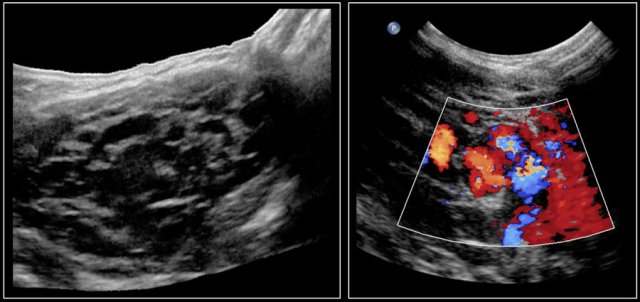

In Graves disease the thyroid gland is also enlarged and shows an increased perfusion.

On color Doppler it has been described as an inferno in red and blue.

Here an image of a 16-year-old girl with hyperthreoidism.

A diffusely enlarged thyroid gland is seen with hyperemia.

The final diagnosis was Graves disease.